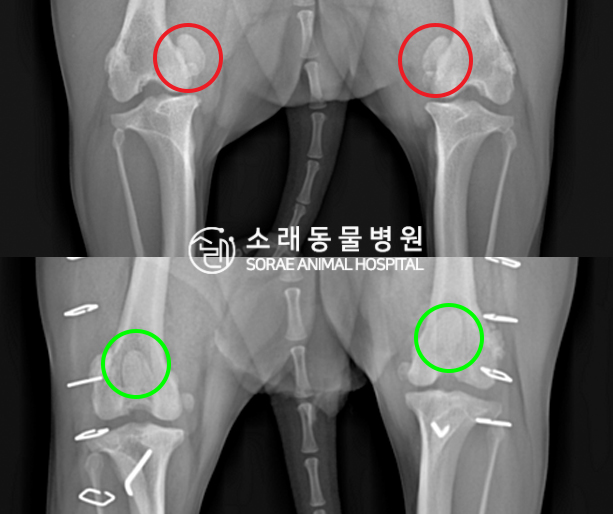

수술전과 수술후에 촬영한 설이의 슬개골

방사선 사진입니다. 나란히 놓고 비교해보니

슬개골의 위치에 확연한 차이가 있는 것을

확인해 볼 수 있는데요. 내측으로 탈구되어 있던

슬개골이 원래 제자리인 활차구에 예쁘게

자리 잡고 있는 모습을 확인할 수 있었습니다.